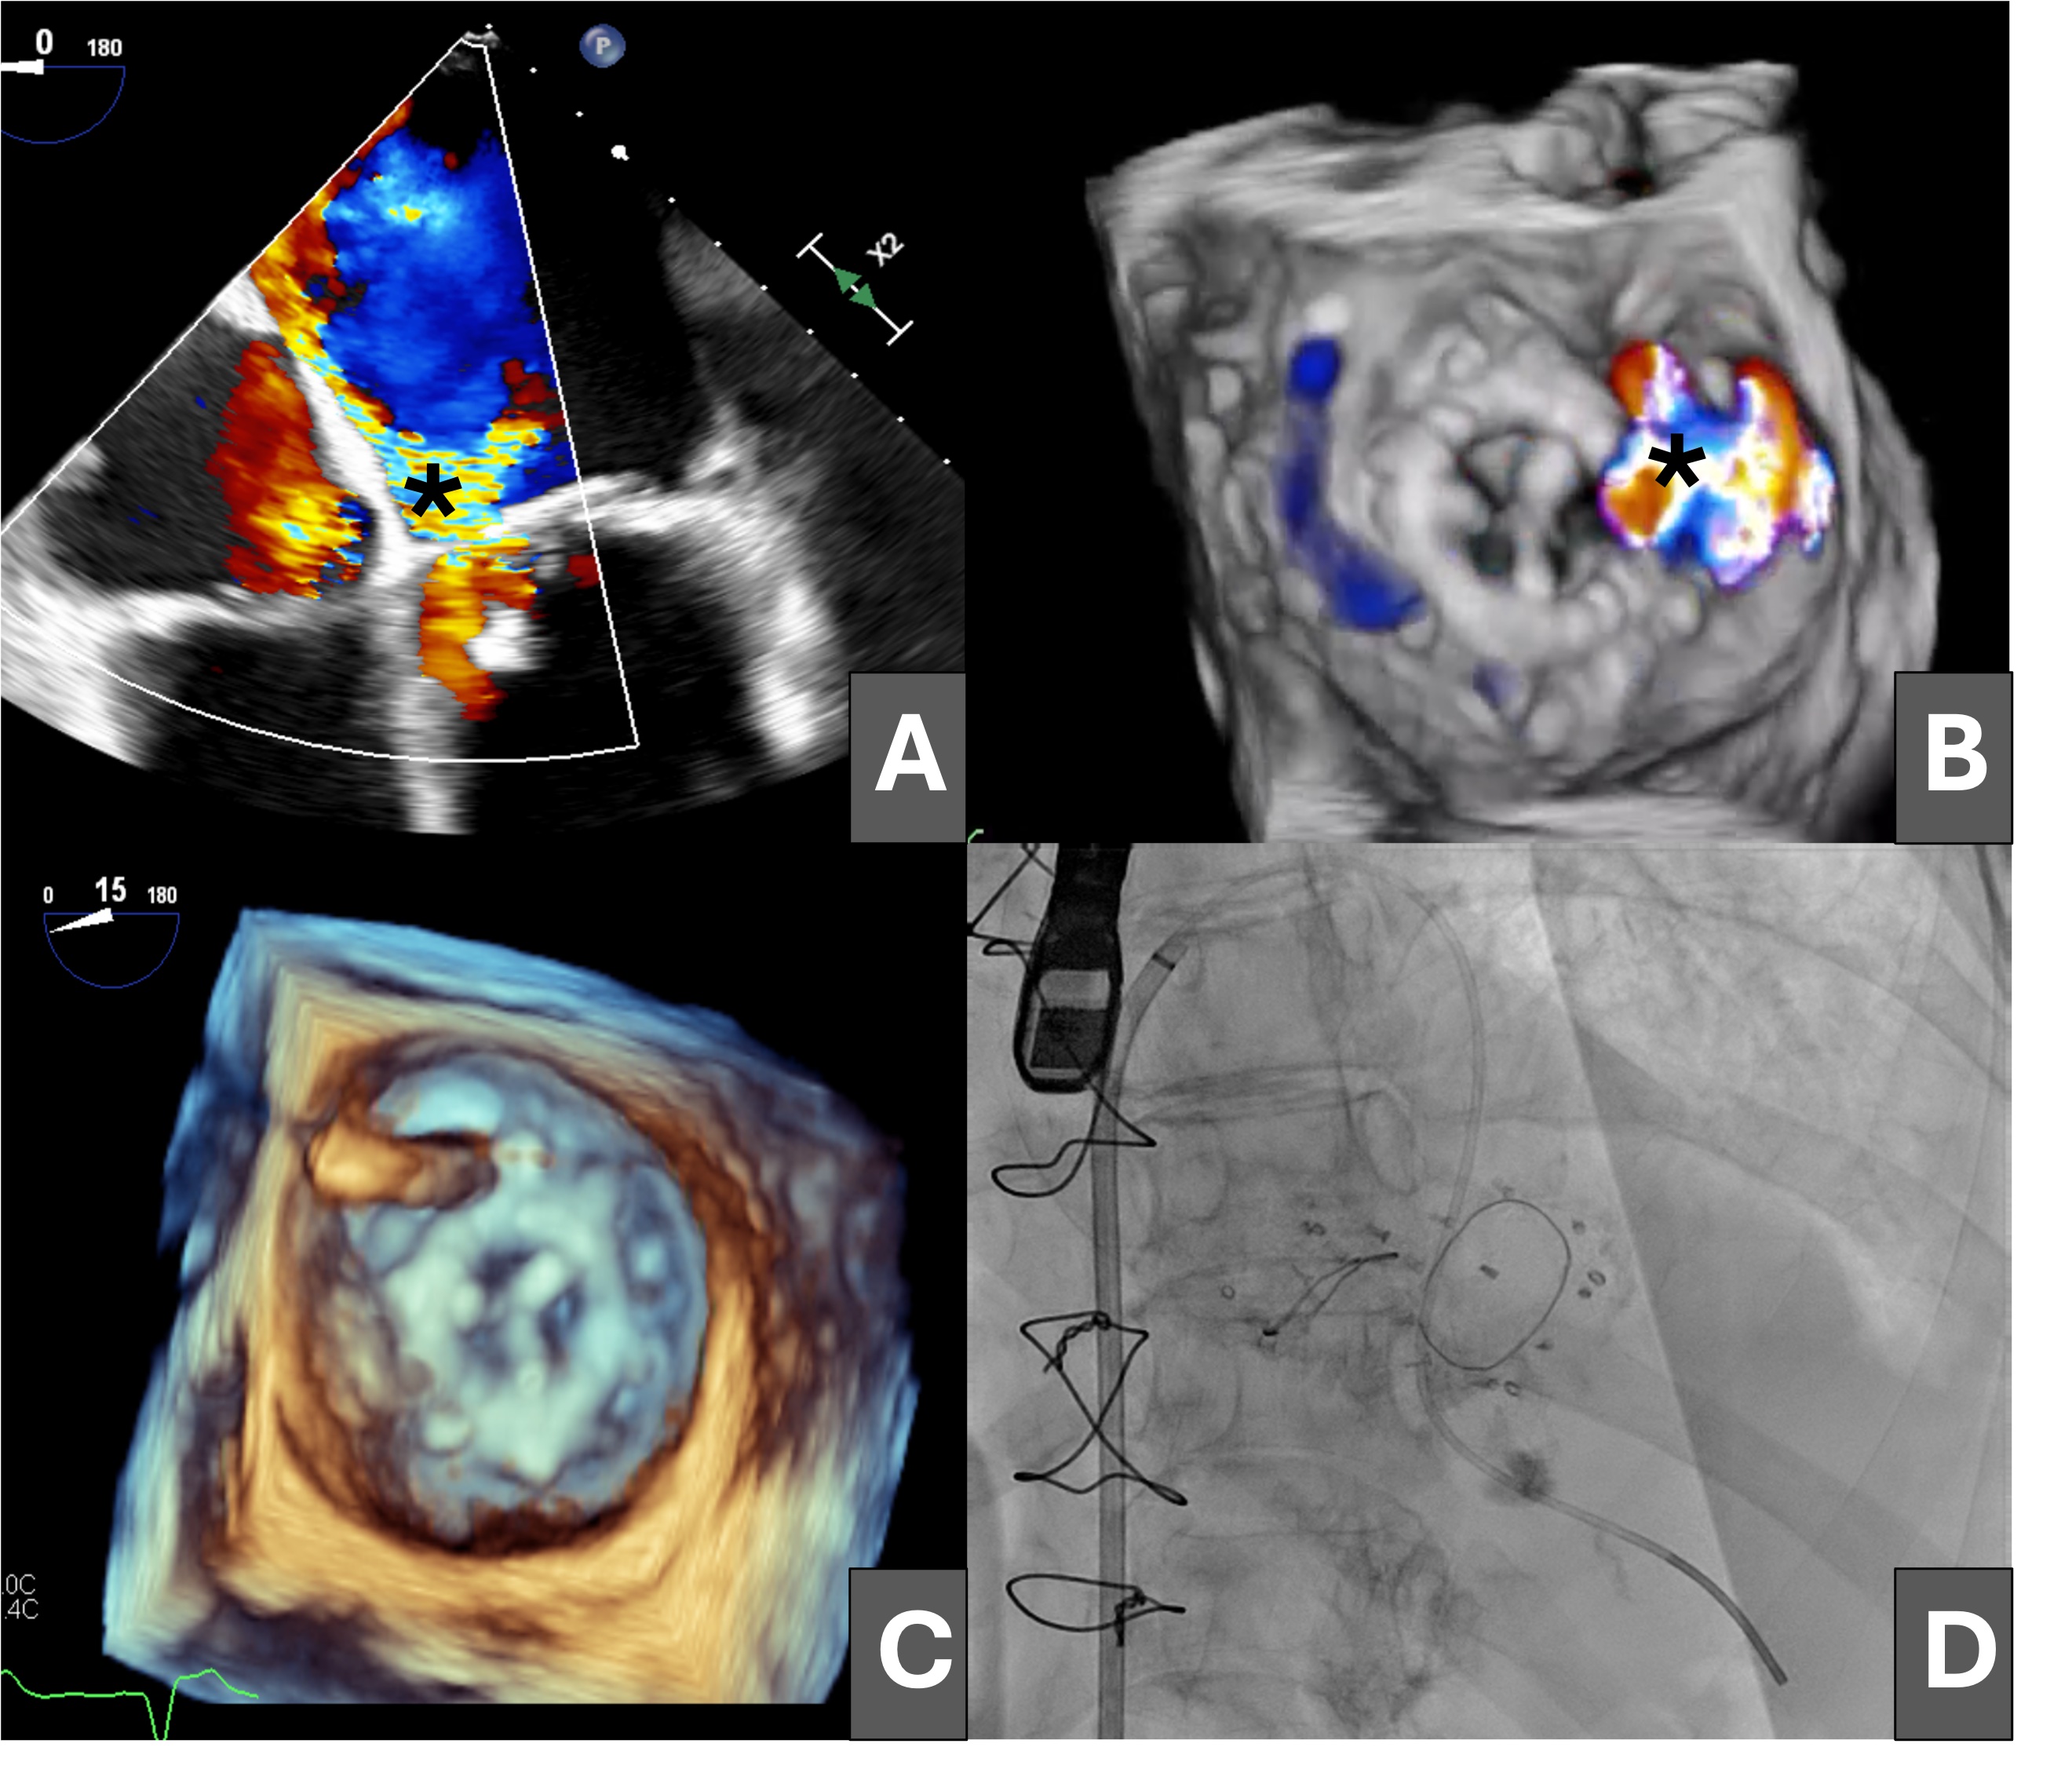

Subsequently, a 14 × 5-mm Amplatzer Vascular Plug III (VP3, Abbott) was advanced through the defect, but it prolapsed into the left atrium (Figure 2A and B). The dehiscence was crossed again, establishing an arteriovenous loop by snaring the guidewire in the ascending aorta (Figure 2C) and maintaining the venoarterial circuit; however, stability of the VP3 device could not be achieved because of the large size of the leak (Figure 2D).